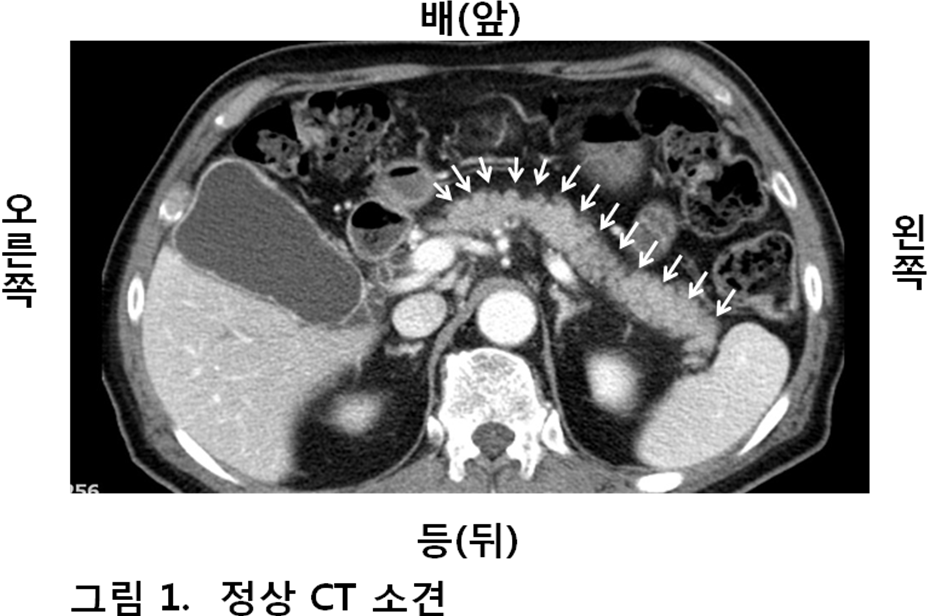

복부 통증은 췌장암의 초기 증상 중 하나로 알려져 있습니다. 일반적으로 통증은 복부 중앙이나 상부에서 느껴지며, 등으로 방사될 수 있습니다. 이 통증은 심한 경우가 많으며, 일상적인 활동을 하는 데 어려움을 줄 수 있습니다.